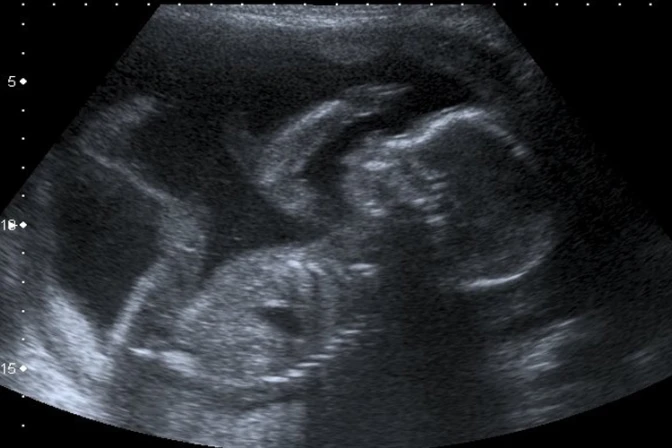

Uno de los puntos de la entrevista que mayor controversia causó fue cuando Zúñiga afirmó que "un bebé en gestación no tiene conciencia del dolor, ya que es una célula individual que, después de unos días, sigue siendo un diminuto conjunto de células sin ningún rasgo anatómico (…) un feto no puede ser consciente del dolor hasta el final del embarazo, porque hasta entonces su cerebro no está lo suficientemente desarrollado".

Declaraciones que son refutadas por la docente de la UC, quien afirma que se sabe que los estudios respecto a este tema son muchos y con diversos resultados, que no permiten sacar una conclusión absoluta.

"Algunos estudios afirman que el feto estaría en una especie de estado de inconsciencia, que no le permitiría sentir dolor, pero otros concluyen que siente dolor desde las 20 semanas de desarrollo. En cualquier caso, eso no puede ser un argumento válido para autorizar el aborto. Sería casi como afirmar que es posible matar a una persona ya nacida que se encuentra en estado de coma o inconsciencia, porque no puede sentir dolor", aseguró.